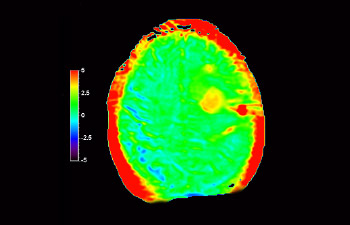

Cerebro con glioblastoma

3D APT

Mayor fiabilidad diagnóstica en neurooncología